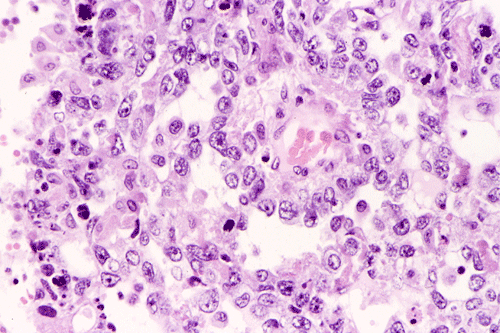

Histopathology of surgical specimen:

A survey at low-magnification shows a necrotic neoplasm (Panel F). The tumor cells arrange in different patterns. The tumor cells are densely packed in some areas but loosely packed in other areas.  At medium-magnification, several different patterns of architecture are disclosed. The most commonly encountered pattern in this case is a reticular-microcystic arrangement of cells (Panel G). In a significant amount of other areas, there are hypocellular to myxoid non-neoplastic stroma lined by a single layer of neoplastic cells (Panel H, I). The tumor cells have moderate to large nuclei with substantial pleomorphism. The chromatin is clumpy and hyperchromatic (Panel J). In some areas the tumor cells has an hepatoid appearance featured by a smaller nuclei with substantial amount of amphophilic cytoplasm (Panel K). Schiller-Duval bodies are occasionally noted (Panel L). A variable number of eosinophilic globules are also present and they are strongly positive for periodic acid-schiff (PAS) reaction (Panel M). Results of immunohistochemistry are as follows:

Yolk sac tumor arising in the thymus often have extensive invasion into the adjacent tissue. In this cases, the tumor is still confined. The histology is quite typical for a yolk-sac (endodermal sinus) tumor. The reticular-microcystic pattern being illustrated here is the most common pattern being encountered.  Only a small number of Schiller-Duval bodies are present. The large cells with hepatoid look correspond to the hepatoid pattern in yolk sac tumor. The solidly arranged sheets of tumor raise the possibility of an embryonal carcinoma. However, the nuclear pleomorphism, although significant, is still short of that from embryonal carcinoma. The extracellular, PAS(+), eosinophilic hyaline globules are also typical for yolk sac tumor. These globules are often immunoreactive for a-fetal protein and a-1-antitrypsin. In our case, they are only positive for a-1-antitrypsin. The lack of CD30 immunoreactivity, again, does not support a diagnosis of embryonal carcinoma.

Yolk sac tumors exhibit a wide range of histologic patterns that differ considerably from each other. In most cases, a mixed histologic pattern is present and, not infrequently, one or two patterns may predominate. The most common pattern is the microcystic-reticular pattern. The other histologic patterns included endodermal sinus, solid, alveolar-glandular, polyvesicular vitelline, myxomatous, macrocystic, papillary, intestinal, hepatoid, and spindle cell. Although there is a rich variation in architecture, the variations in cytologic features are less impressive. The tumor cells are medium to large and have clear to pale, granular cytoplasm. Hobnail cells are not uncommon and often seen with the papillary pattern. The nuclei are large, vesicular, and contain prominent nucleoli. Yolk sac tumors are mitotically active. Necrosis and hemorrhage are common.

The microcystic-reticular pattern is characterized by a loose vacuolated network with small cystic spaces or microcysts that give rise to a meshwork of communicating space. The microcysts are lined by flat, pleomorphic, epithelium-like cells with large hyperchromatic or vesicular nuclei. The myxomatous pattern is similar to the microcystic pattern but is loosely packed and contains mucoid material.